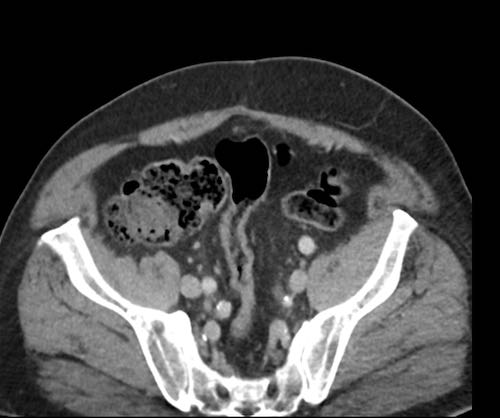

Ca lâm sàng 2

Cuộn qua các lát cắt.

Bạn có thể phát hiện tất cả các tổn thương cấy ghép phúc mạc không?

.jpeg)